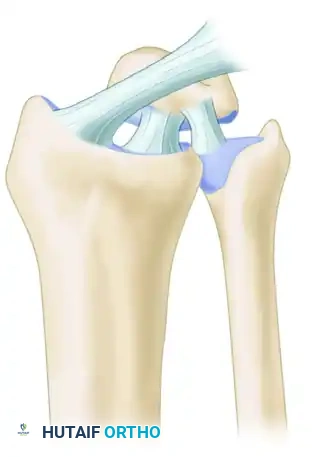

Lichtman expanded upon carpal kinematics by describing the carpus as an oval ring. In this model, the proximal and distal carpal rows act as semirigid posts stabilized by robust interosseous ligaments.

* Normal, controlled mobility occurs primarily at the scaphotrapezial and triquetrohamate joints.

* Pathomechanics: Any break in this ring—whether osseous (e.g., scaphoid fracture) or ligamentous (e.g., scapholunate dissociation)—destabilizes the kinematic chain.

Depending on the location of the break, the lunate will fall into an abnormal posture, producing either a Dorsal Intercalated Segmental Instability (DISI) or a Volar Intercalated Segmental Instability (VISI) deformity.

Stage I: Scapholunate Dissociation

The injury initiates radially with the disruption of the scapholunate (SL) interosseous ligament and the volar radioscaphocapitate ligament. This results in rotatory subluxation of the scaphoid.

Stage II: Capitolunate Disruption

As the force propagates ulnarly, the space of Poirier (a weak area in the volar capsule between the capitate and lunate) is breached. The capitate subluxates dorsally relative to the lunate.

Stage III: Lunotriquetral Disruption (Perilunate Dislocation)

The force continues through the lunotriquetral (LT) interosseous ligament. The entire carpus dislocates dorsally, leaving only the lunate articulated with the distal radius.

Stage IV: Lunate Dislocation

The final stage involves the failure of the dorsal radiocarpal ligament. The capitate is driven proximally, forcing the lunate to rotate and dislocate volarly into the carpal tunnel, often causing acute median nerve compression.